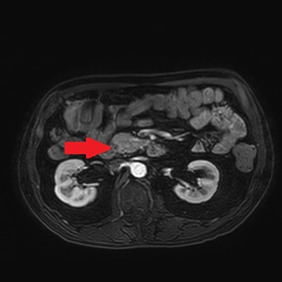

An abdominal ultrasound showed no signs of cholecystitis. A computed tomography (CT) scan revealed dilatation of the intrahepatic and extrahepatic bile duct as well as enlargement of the pancreatic head with ill-defined margins. Following hospitalization, an endoscopic sphincterotomy and endoscopic retrograde biliary drainage with 8.5 fr × 9 mm plastic stent were performed. The brush cytology of the common bile duct performed during the ERCP (endoscopic retrograde cholangiopancreatography) was positive for adenocarcinoma type malignant cells whose cytomorphological and immunophenotypic aspects were compatible with biliopancreatic primary. A magnetic resonance imaging (MRI) scan showed a 2 cm hypointense mass in the pancreatic head, with no signs of invasion in the main blood vessels (Figure 1).